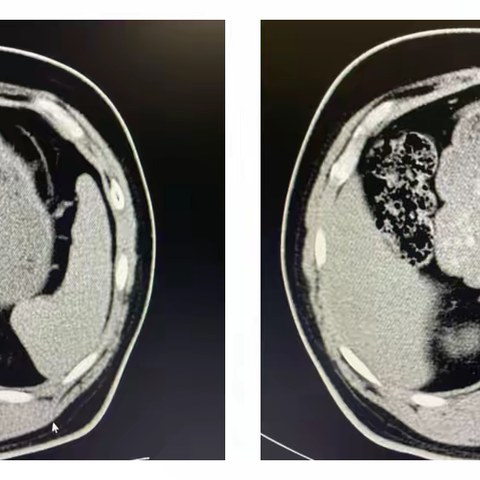

肾上腺结节,我该怎么办?

南阳首次,省内领先-肾上腺静脉取血术